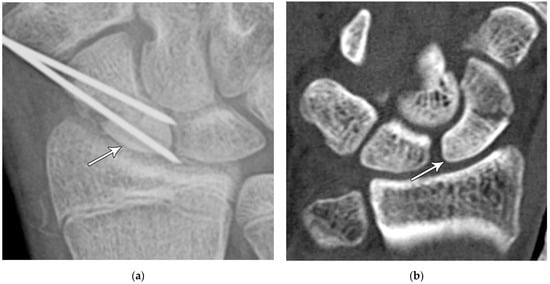

Figure 5. (a) PA radiograph showing marked sclerosis (arrow) of the proximal pole of the scaphoid after a scaphoid fracture. (b) Coronal reformatted CT in a different patient showing sclerosis (arrow) of the proximal pole of the scaphoid after a scaphoid fracture, indicating osteonecrosis.

Common scaphoid fracture complications include avascular necrosis and nonunion [10]. Avascular necrosis is a dreaded outcome resulting from the loss of the proximal arterial supply due to the distal entry point of nutrient vessels. This retrograde perfusion of the proximal pole makes it vulnerable to losing its vascular supply when fractured. Sclerosis of the proximal pole indicates osteonecrosis (Figure 5). With scaphoid nonunion, biomechanical alterations contribute to rapidly progressive degenerative arthritis and instability referred to as scaphoid nonunion advanced collapse (SNAC) [16]. Nonunion occurs in 5–10% of cases and has a higher incidence in displaced fractures (Figure 6). During wrist extension, the distal scaphoid fragment rotates into flexion while the proximal scaphoid fragment extends with the lunate. The resultant abnormal contact between the distal fragment and radius begins the first stage of degenerative collapse. This progresses into the second stage as scaphocapitate osteoarthritis develops and finally to the third stage with progression to capitolunate osteoarthritis and proximal radial migration of the capitate dorsal to the lunate. Treatment of SNAC wrists, depending on the degree and severity of the osteoarthritic collapse, includes scaphoidectomy with four-corner arthrodesis or wrist fusion [17]. Four-corner fusion helps reduce joint pain while maintaining some range of motion, as opposed to total wrist fusion (Figure 7). Another option is proximal row carpectomy with resurfacing capitate pyrocarbon implant placement [18].